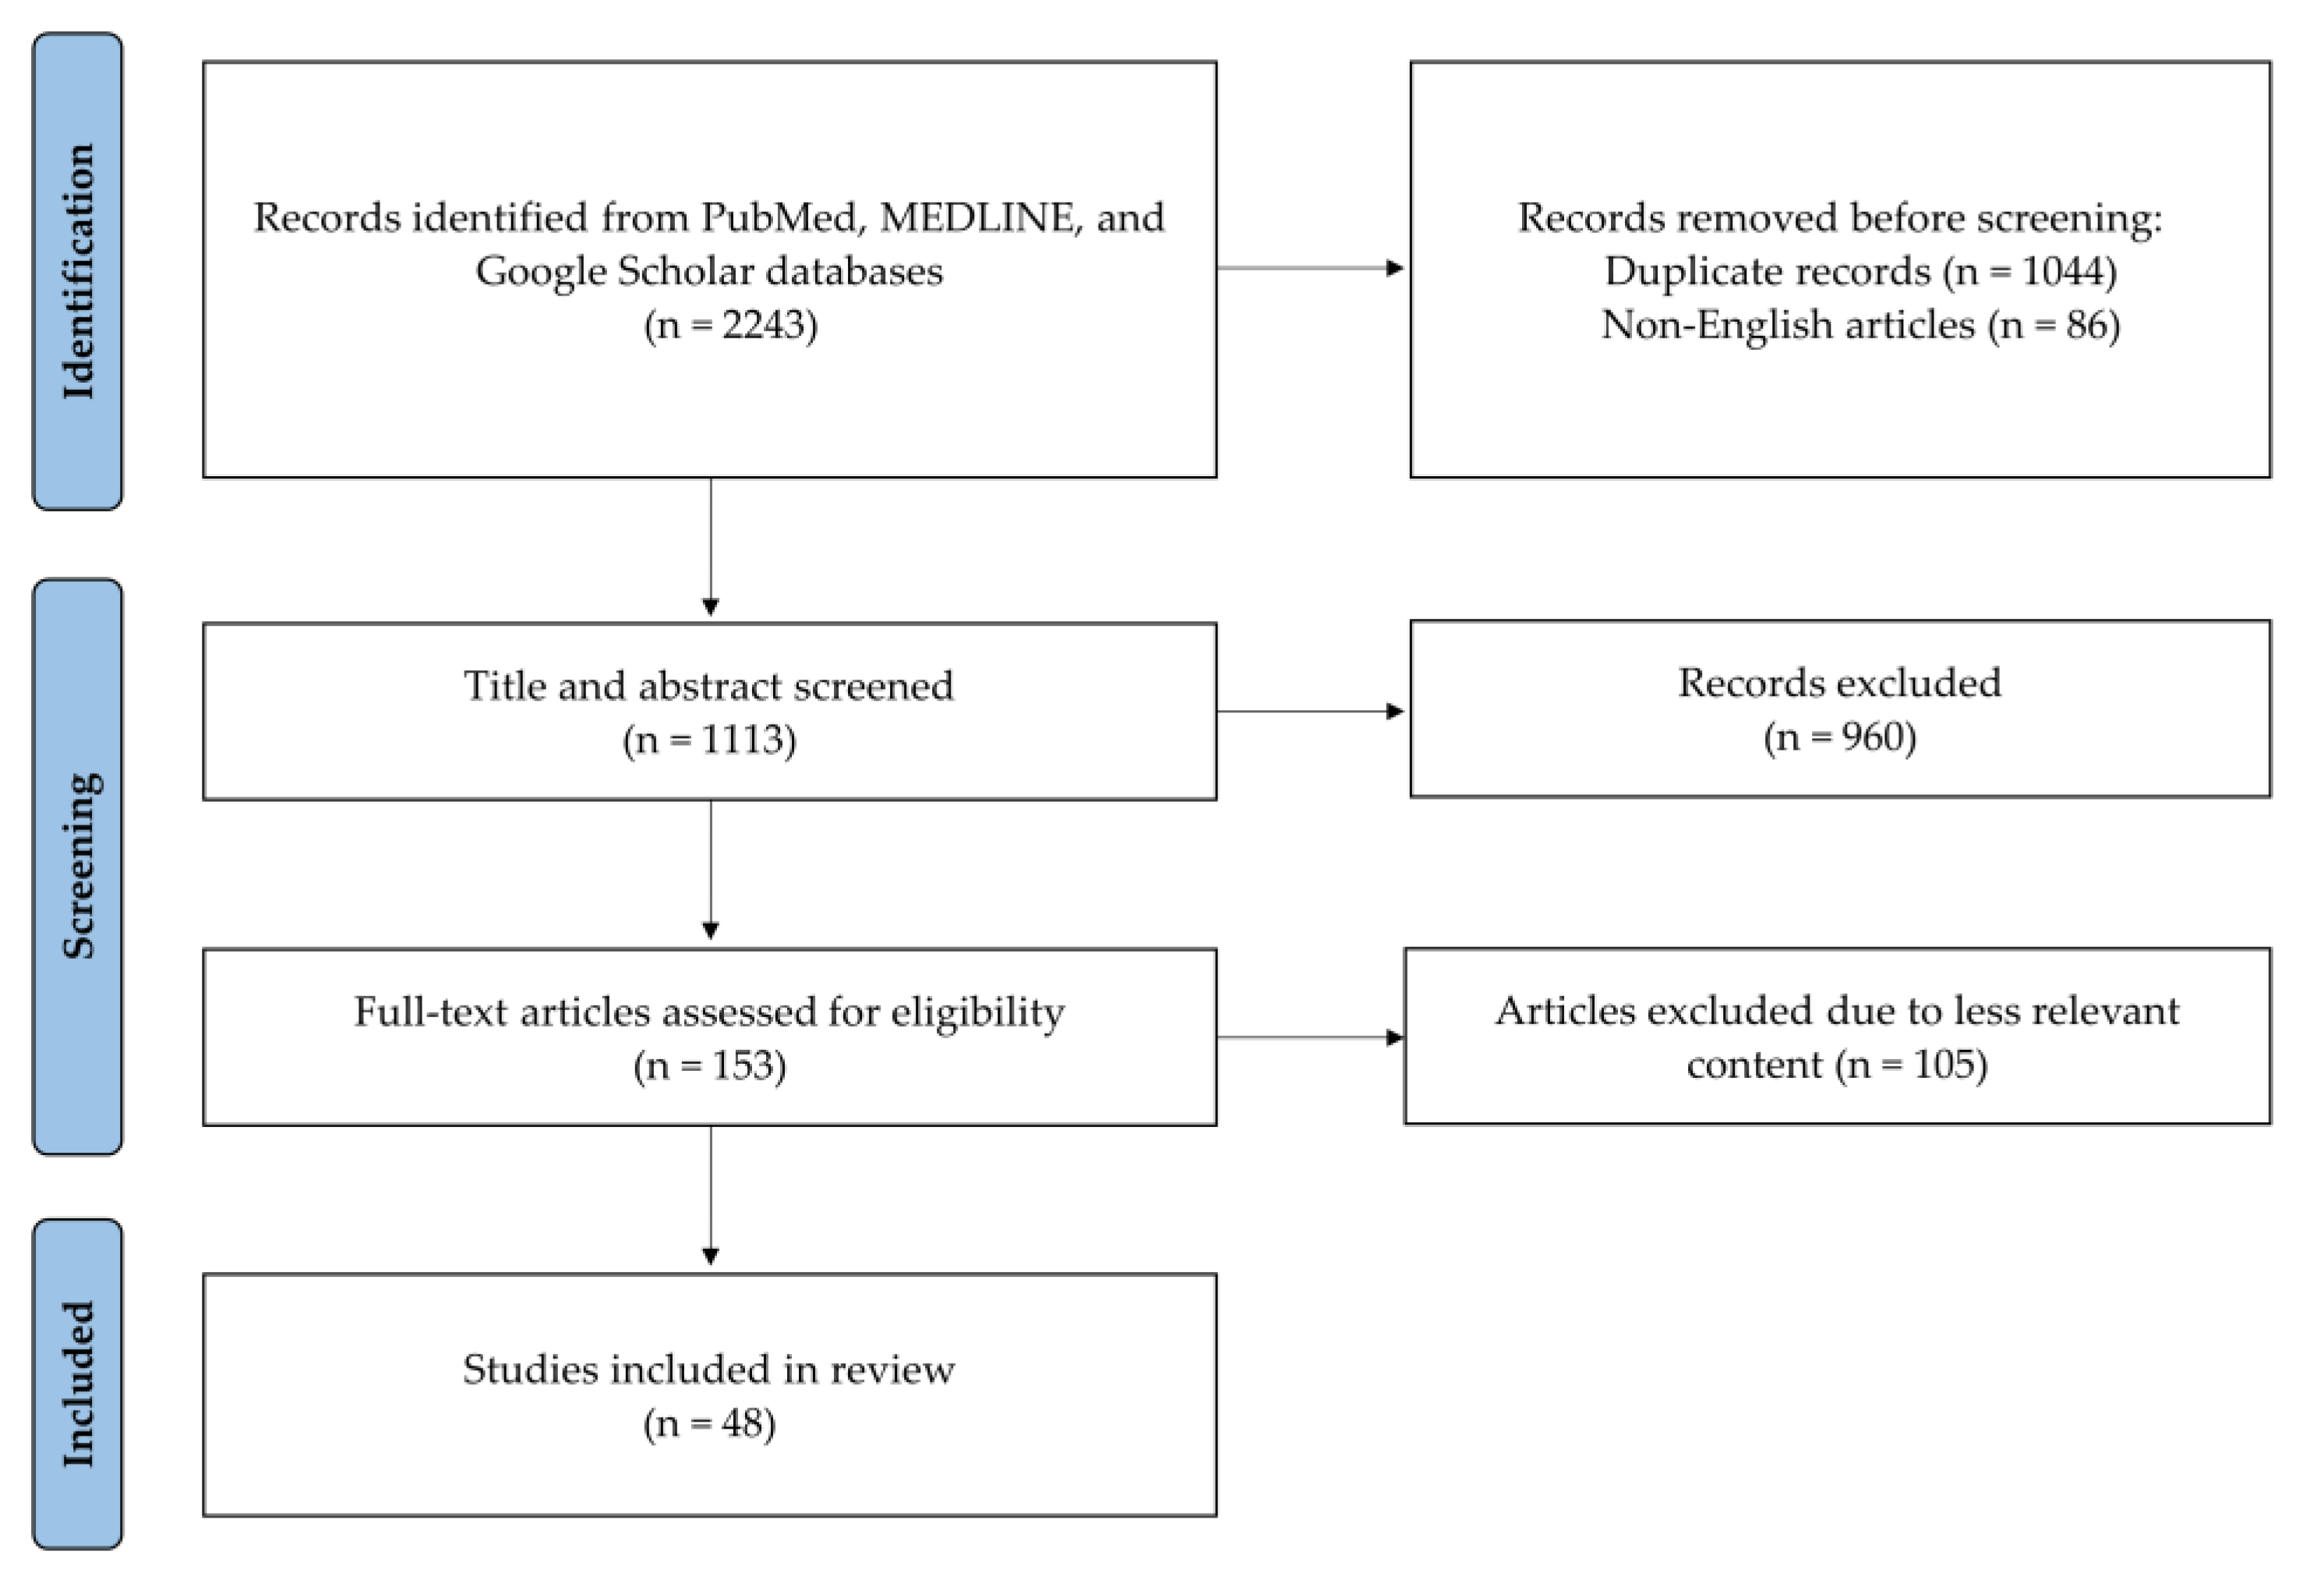

2. Methods